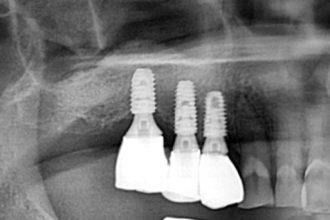

임플란트